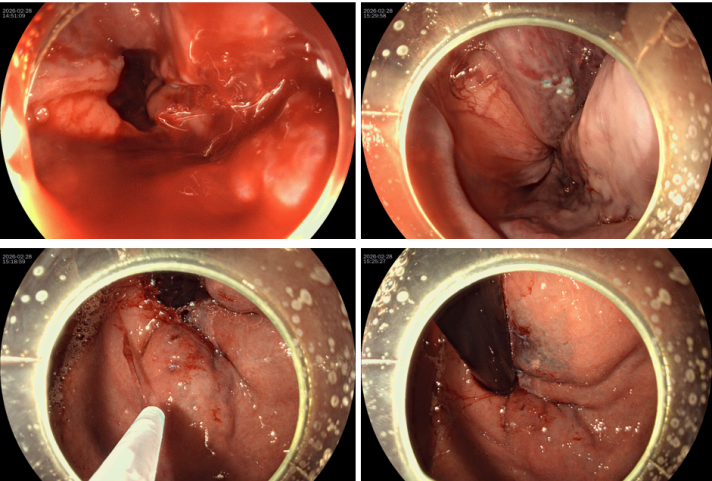

消化二科麻张亮副主任医师第一时间赶赴重症医学科参与救治,紧急为刘先生行胃镜检查,发现其食管中下段有多条直径0.5-2.0cm的曲张静脉,胃底也有3条1.0-1.5cm的曲张静脉,且食管距门齿38cm处有0.3*0.3cm的静脉破口正活动性喷血,胃腔内积有大量血凝块。

危急时刻,麻张亮副主任医师精准操作,在食管喷血处注射组织胶+硬化剂,出血瞬间停止。随后又对胃底及食管其他曲张静脉进行针对性治疗,整个操作干脆利落、精准高效。目前刘先生恢复良好。